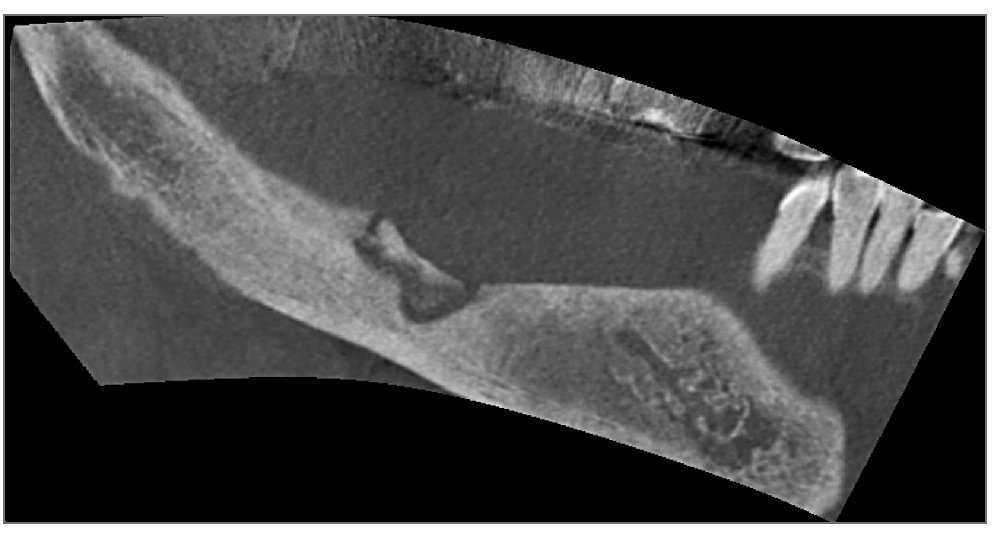

Como los exámenes radiográficos sugirieron osteomielitis en la mandíbula posterior derecha (fig. 1) y en el área de los premolares superiores izquierdos, se llevó a cabo una secuestrotomía en maxilar y mandíbula. Los resultados serológicos mostraron que la CTX sérica (telopéptido c-terminal del colágeno tipo I), el marcador que indica la tasa de supresión del recambio óseo1, se encontraba marcadamente disminuida (10 pg/ml).

Figura 1 (arriba). Lesión osteolítica mal definida en mandíbula derecha en una imagen de tomografía volumétrica digital (TVD).